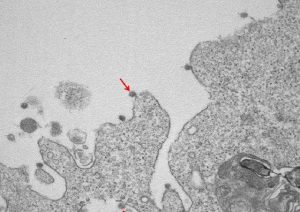

Laboratori në Lombaridi në Spitalin Sacco në Milano ka publikuar një foto sesi duket koronavirusi. Në imazhet e mikrografisë elektronike tregohen grimcat virale të bashkangjitura në membranat qelizore dhe kurorën e tyre tipike të glikoproteinave sipërfaqësore.

Kanë qenë Antonella Tosoni dhe Beatrice Marchini, ata që bënë vëzhgimet nën mikroskopin elektronik dhe prodhuan imazhet që tregojnë virusin vdekjeprurës. Në të parën, me një zmadhim prej 30000X, vërehen grimcat virale të SarsCov2 (të treguar nga shigjeta), të bashkangjitura në membranat në sipërfaqe dhe qelizat e brendshme, të përdorura për izolim.